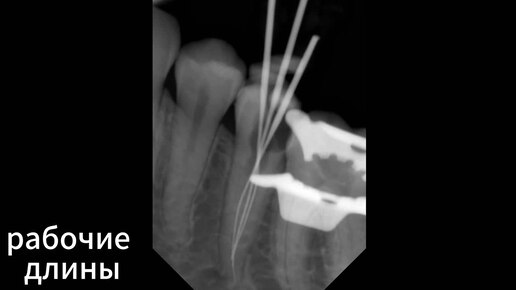

Аномалия - 3 канала в нижнем 5 зубе, сложная эндодонтия Стоматология Parodent, СПб